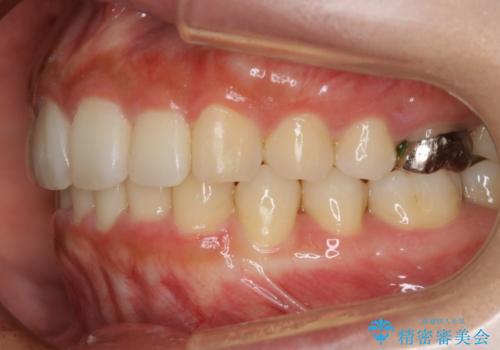

【非抜歯】インビザラインでガタつきと口元を改善!非抜歯でも印象が変わる矯正治療

- 歯のガタつきと口元の突出感を主訴に来院されました。

装置の希望がインビザラインだったため、非抜歯でインビザラインの特徴を最大限に生かして行う矯正治療を選択しました。

顔貌写真でも明らかに口の閉じやすさやEラインが改善している様子が分かります。